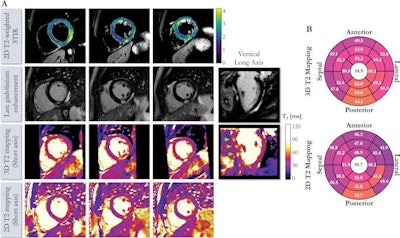

Although clinical guidelines recommend the use of established T2 mapping sequences to detect and quantify myocarditis and edema, these sequences are performed in two dimensions with repetitive breath holds and provide only limited coverage of the heart, according to the researchers. In this study, the authors sought to further evaluate an accelerated, high isotropic resolution, free-breathing 3D whole-heart mapping sequence they had previously developed.

The researchers compared the reproducibility of their 3D whole-heart free-breathing technique with 2D breath-hold T2 mapping in phantoms as well as eight healthy participants. They also investigated its clinical performance in 25 patients with suspected myocarditis.

The whole-heart T2 maps were acquired in a mean time of six minutes, 53 seconds at 1.5 mm3 resolution, according to the researchers.

Using the 3D T2 mapping technique, the researchers found that patients with suspected myocarditis had prolonged myocardial T2 values (68 msec ± 7) in comparison with participants without a history of heart disease (51 msec ± 3).

In 21 of the 25 patients, interpretations were the same between the two methods. However, in four (16%) cases, cardiac inflammation was found to be present with high confidence on the 3D T2 mapping images but deemed to be inconclusive on the corresponding 2D T2 mapping images.